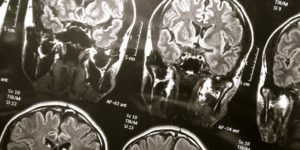

El hallazgo científico fue protagonizado por Frontiers in Aging Neuroscience, a través de un electroencefalograma de un paciente muerto por un paro cardiaco mientras se registraba su actividad cerebral.

El cuerpo estudiado era de una persona de 87 años y reveló que el cerebro quedó en coordinación durante la transición a la muerte y después de la misma. Esto revela que en ese tiempo de cambio natural, puede existir el momento del recuerdo.